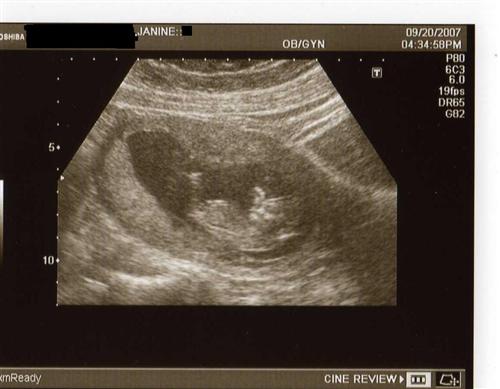

Had 12 week sono last night w/pics

The baby was sleeping, I had to cough to wake it up. You can see how it was sleeping...with it's hands behind his/her head-I guess it's comfy in there! Oh, and I think our child looks like an alien...

Does anyone know what the other black circle to the right is? We didn't think to ask. If it was another baby, it would be full, so I don't think it is that.